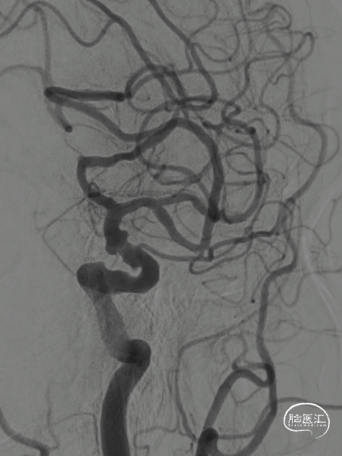

左侧颈内动脉造影:大脑前动脉A2段瘤样扩张,夹层可能;颈总动脉起始部扭曲。

经右侧桡动脉通路,赛诺神畅 6F-105 APEX TRA®经桡远端通路导引导管内衬SIM2导管、泥鳅导丝,左侧颈内动脉顺利直接到位海绵窦段行3D造影。

动脉瘤无明显变化;A1开口角度较大,输送支架需注意导管是否失位。

支架头端锚定后造影定位。

术后影像。